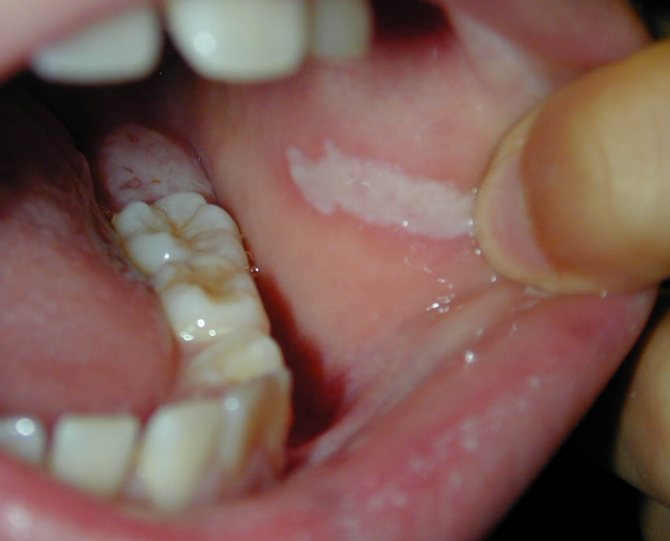

- Лейкоплакия. При лейкоплакии верхние слои эпителия уплотняются и грубеют. Связано это с воспалительными процессами на слизистой оболочке полости рта. Лейкоплакию разделяют на три подвида: плоскую или простую, веррукозную, также называют лейкокератоз или бородавчатая, а также эрозивную.

Лейкоплакия ротовой полости — одно из предраковых состояний.